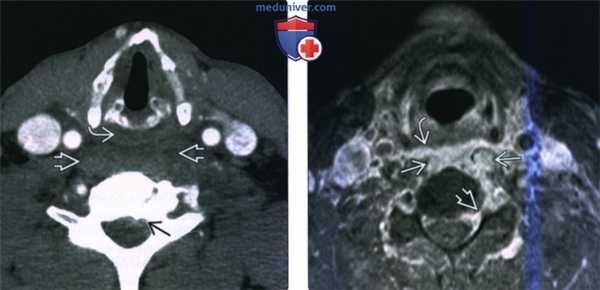

(Слева) КТ с КУ, пациент с септицемией, аксиальная проекция. В анамнезе имеются сведения об употреблении наркотических препаратов. Основной жалобой является интенсивная боль в шее. Имеется выраженное утолщение предпозвоночных тканей со смещением гортаноглотки кпереди. Имеются признаки эпидуральной флегмоны.

(Справа) MPT Т1ВИ FS с КУ, аксиальная проекция, этот же пациент. Интенсивное накопление контраста в предпозвоночных мягких тканях с инфильтрацией длинных мышц шеи и заглоточного пространства. Слева имеются признаки поражение эпидурального пространства и межпозвоночного отверстия.